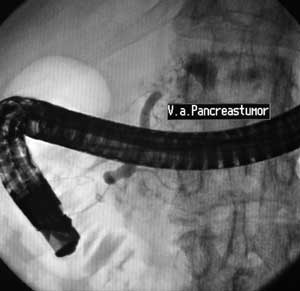

Рентгеноскопия + эндоскопия = ЭРХПГ.

Рис. 2. Опухоль тела поджелудочной железы. Симптом “стоп” при введении рентгенконтрастного вещества в панкреатический проток.